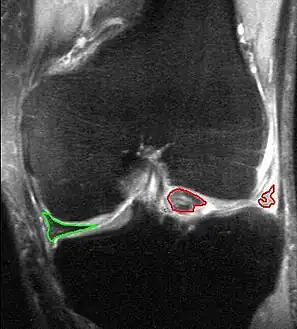

MRI of right knee revealing intra-articular and bucket-handle medial meniscus tear with the displaced fragment located in the intercondylar notch.

Bucket-handle tear of the lateral meniscus (red). Medial meniscus intact (green). MRI, coronal T2 *-weighted GRE sequence.

X-ray images (normally during weightbearing) can be obtained to rule out other conditions or to see if the patient also has osteoarthritis. The menisci themselves cannot be visualised with plain radiographs. If the diagnosis is not clear from the history and examination, the menisci can be imaged with magnetic resonance imaging (an MRI scan). This technique has replaced previous arthrography, which involved injecting contrast medium into the joint space. In straightforward cases, knee arthroscopy allows quick diagnosis and simultaneous treatment. Recent clinical data shows that MRI and clinical testing are comparable in sensitivity and specificity when looking for a meniscal tear.